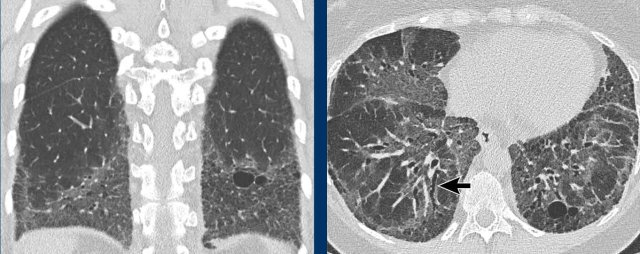

These images are of a 66-year-old man, who is a smoker and complaints of dyspnoe.

Study the image.

What is the most characteristic finding?

What is the most likely diagnosis?

Findings

There are multiple cysts.

Some are irregularly shaped and some have a cheerio sign as a result of cavitation within the nodule (white arrows)

There are also some nodules (black arrows).

Discussion

The combination of these findings in a smoker is typical for the diagnosis LCH.

Continue...

On the coronal reconstruction it is obvious, that the cysts predominantly involve the upper and middle lobes and spare the lung bases.

Especially when LCH is still in the nodular phase, this distribution can be a helpful sign in the differentiation of metastases, which have a lower lobe preference.

This is a similar case.

Notice that the cysts predominantly involve the upper and middle lobes.

The pleural recesses are preserved.

The cysts have caused a pneumothorax.